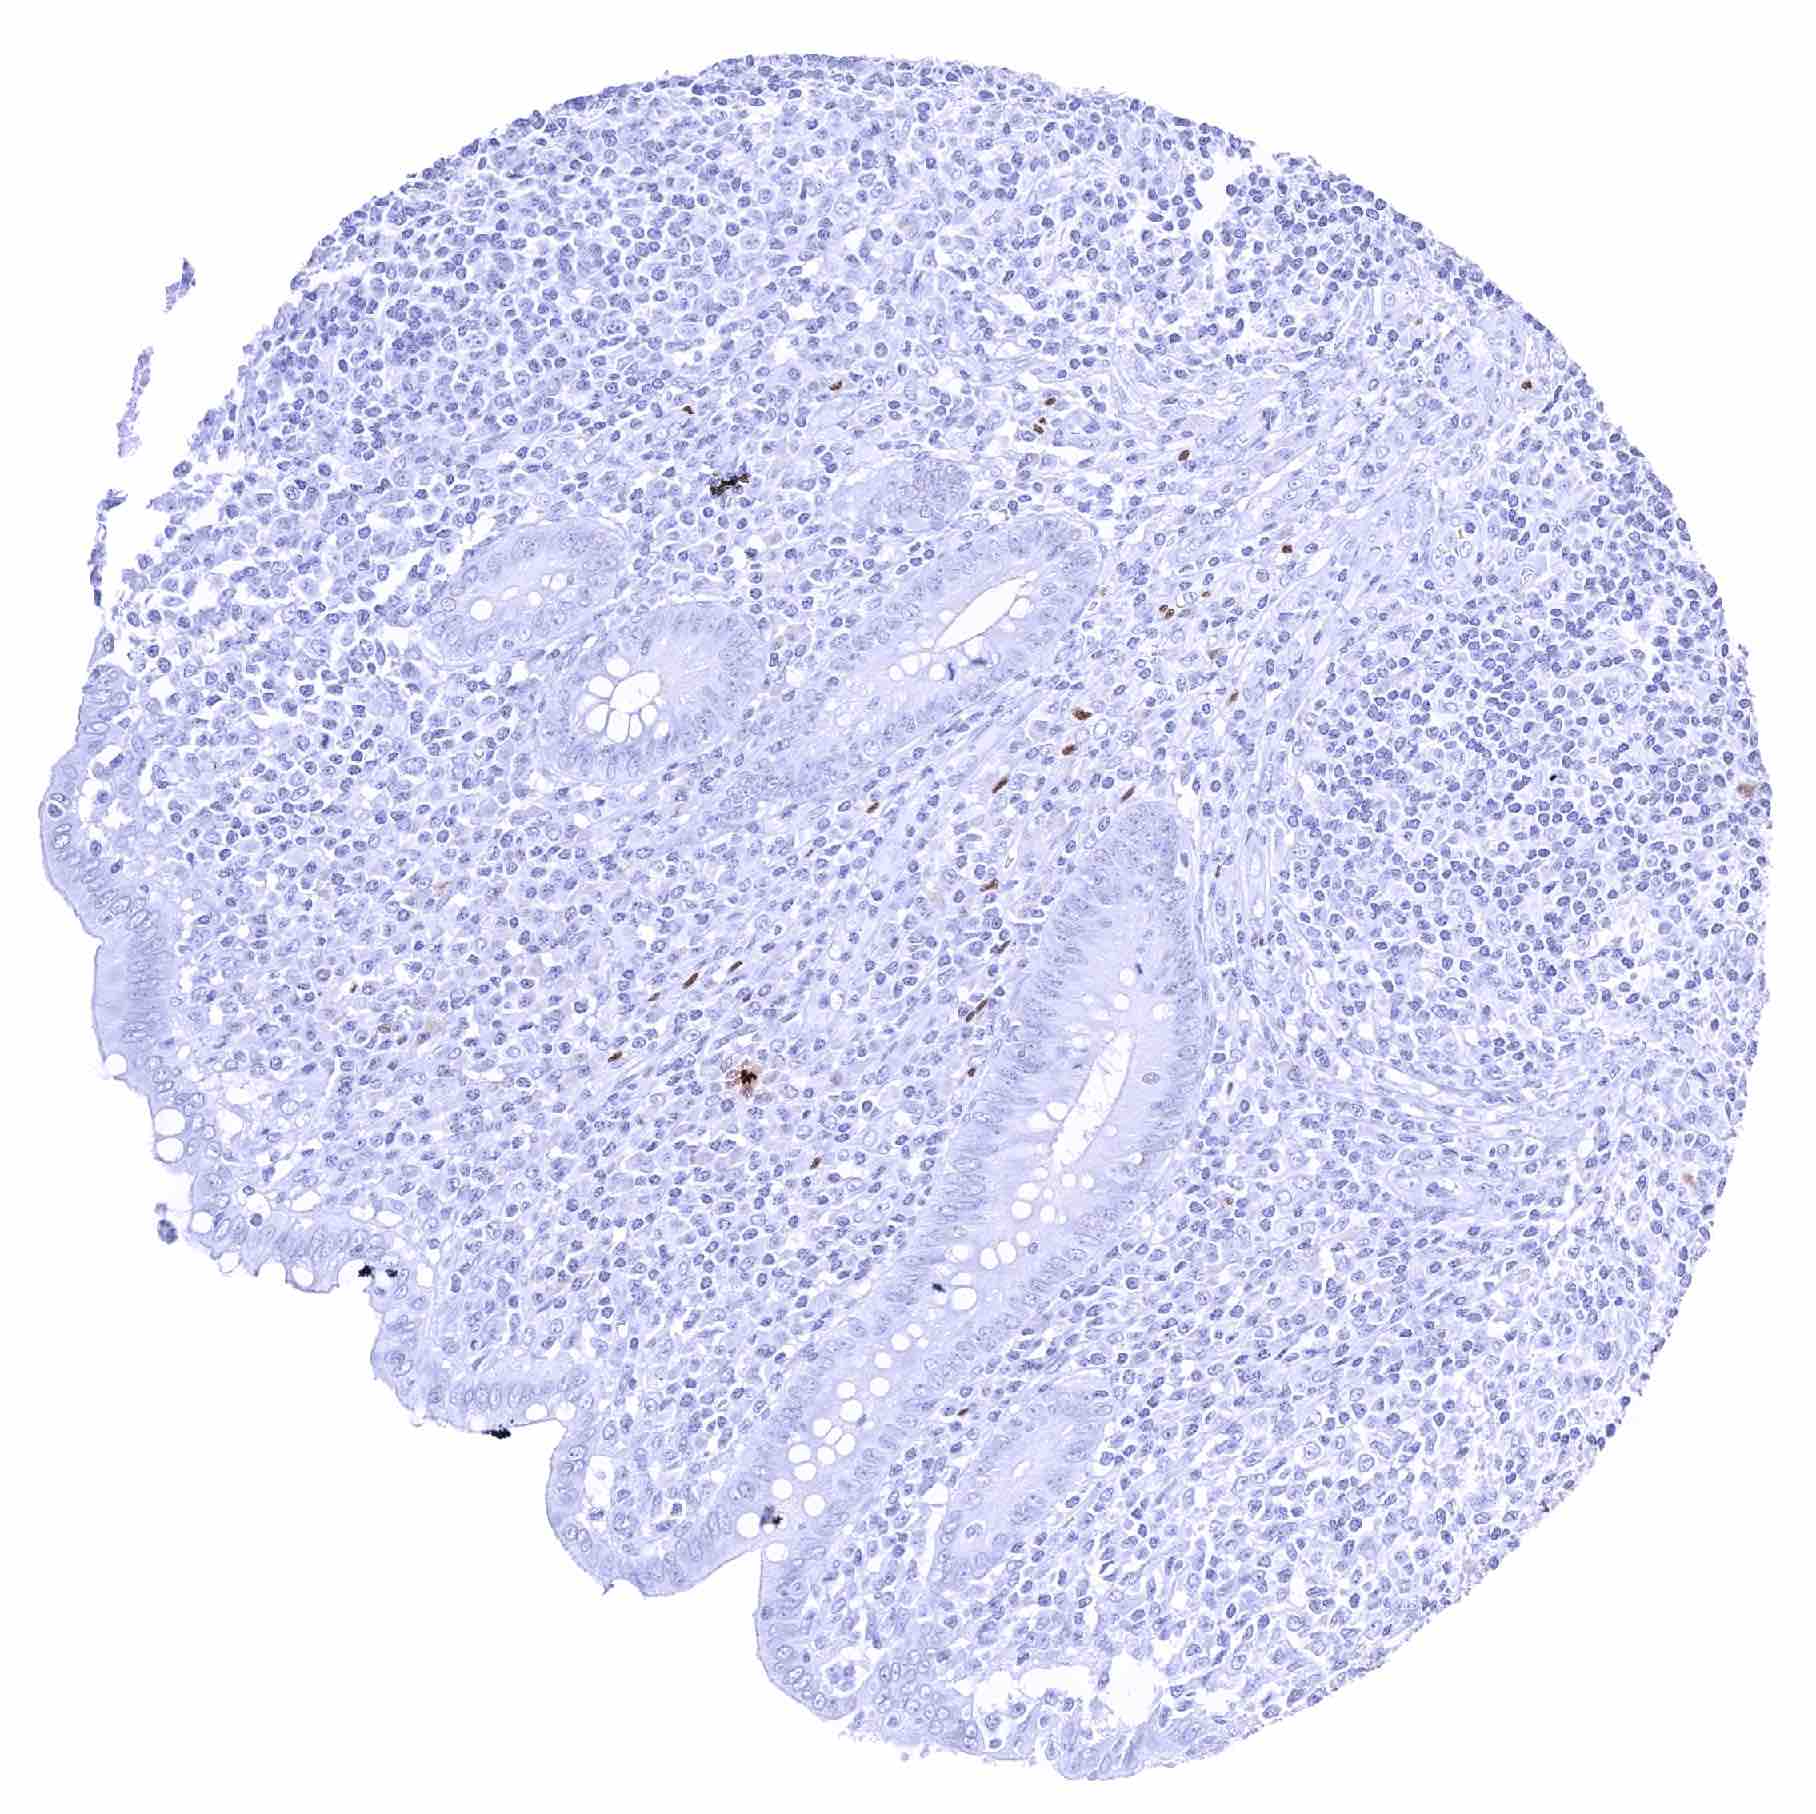

Lymph node